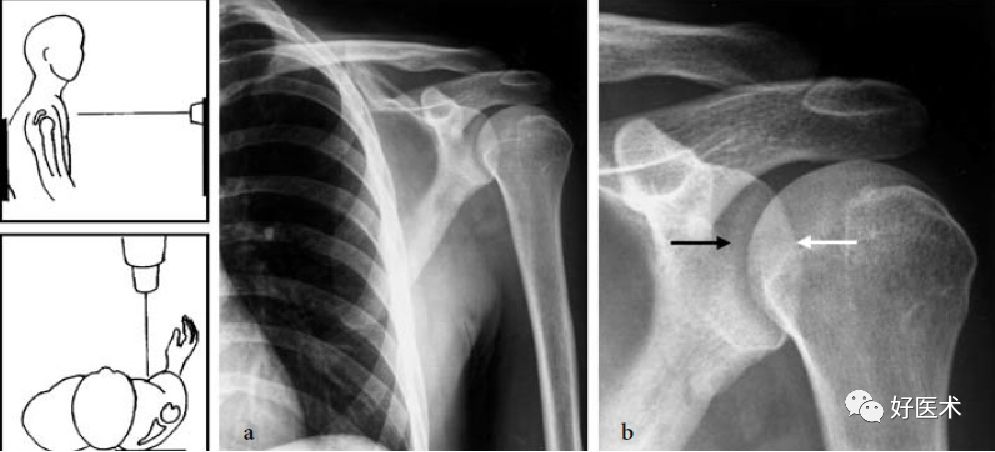

肩关节前后位

肩关节前后位X线检查:患者直立于检查板前,躯体无旋转,X线束平行于地面,水平穿过肩关节

-

由于X线斜切于盂肱关节,故在该X线片上盂臼呈椭圆形

有利于对肩胛骨、肱骨近端以及胸壁的观察

对盂肱关节的评估不理想,上臂处于中位旋转位置

肩关节切线位

受检者处于40度后斜位,要检查的肩关节贴近检查板

肩关节切线位有利于对盂肱关节和肩峰下间隙的显像